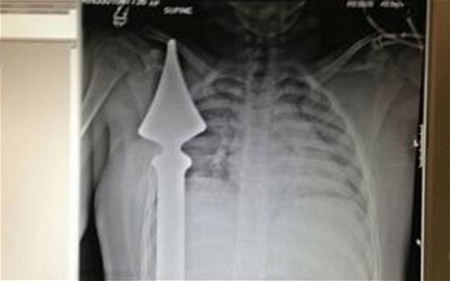

| Hình chụp phim X-Quang cho thấy cọc nhọn hàng rào đâm xuyên qua người cậu bé. |

Sự việc xảy ra khi Josh Hassan, 12 tuổi, sống tại London (Anh) đã bị trượt chân khi đang trèo qua một hàng rào bằng kim loại để lấy trái bóng bị đá văng vào phía bên kia hàng rào. Những cọc nhọn trên đầu hàng rào đã đâm xuyên qua ngực Hassan.

Các bác sĩ cho biết cậu bé Josh đã rất may mắn khi thanh sắt đã không chạm vào bộ phận quan trọng nào trong cơ thể như tim hay phổi. Đáng chú ý, thanh sắt này cắm xuyên qua người cậu bé chỉ cách tim 6cm. Nếu lệch qua một chút, hẳn cậu bé đã không thể được cứu sống.